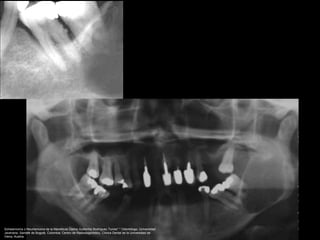

Schwannoma del trigémino, en el cuerpo o en cualquiera de

las ramas.

Schwannoma o Neurilemoma de la Mandíbula Carlos Guillermo Rodríguez Torres* * Odontólogo, Universidad

Javeriana, Santafé de Bogotá, Colombia; Centro de Radiodiagnóstico, Clínica Dental de la Universidad de